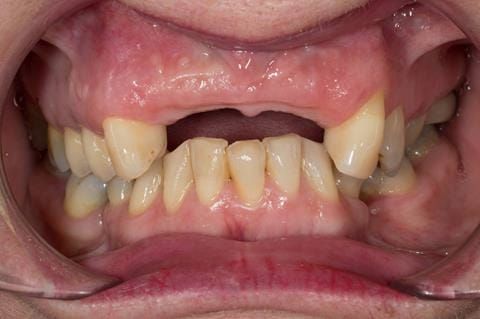

- UR2 peri-radicular periodontitis with a peri-radicular area on the root apex. Retrograde amalgam filling from a previous apicectomy. No visible root canal or root canal filling. Large circumferential marginal gap between the crown and tooth. Large post and core present. Very little tooth structure remaining resulting in a fragile tooth with increased potential for fracture.

- UR1 peri-radicular periodontitis with a small peri-radicular area on the root apex with wide blunderbuss apex. Radio-opaque root canal filling present approximately 3 mm short of the radiographic apex. Large circumferential marginal gap between the crown and tooth. Large post and core present. Very little tooth structure remaining resulting in a fragile tooth with increased potential for fracture.

- UL1 peri-radicular periodontitis with a peri-radicular area on the root apex. Retrograde amalgam filling from a previous apicectomy. Visible root canal space with no sign of root canal filling. Large circumferential marginal gap between the crown and tooth. Large post and core present. Very little tooth structure remaining resulting in a fragile tooth with increased potential for fracture.

- UL2 peri-radicular periodontitis with a peri-radicular area on the root apex. No visible root canal or root canal filling. Large circumferential marginal gap between the crown and tooth. Large post and core present. Very little tooth structure remaining resulting in a fragile tooth with increased potential for fracture.

- High smile line showing gum above gingival zeniths of upper front teeth when smiling. Aesthetic failure of the upper four incisors with inflammation of the gingivae and mis-match of the gingival zenith levels.

- Other than the maxillary incisors the remaining dentition was in marginally better condition being moderately to heavily restored. Many will probably require replacement and restoration from time to time mainly from wear and tear owing to occlusal forces.